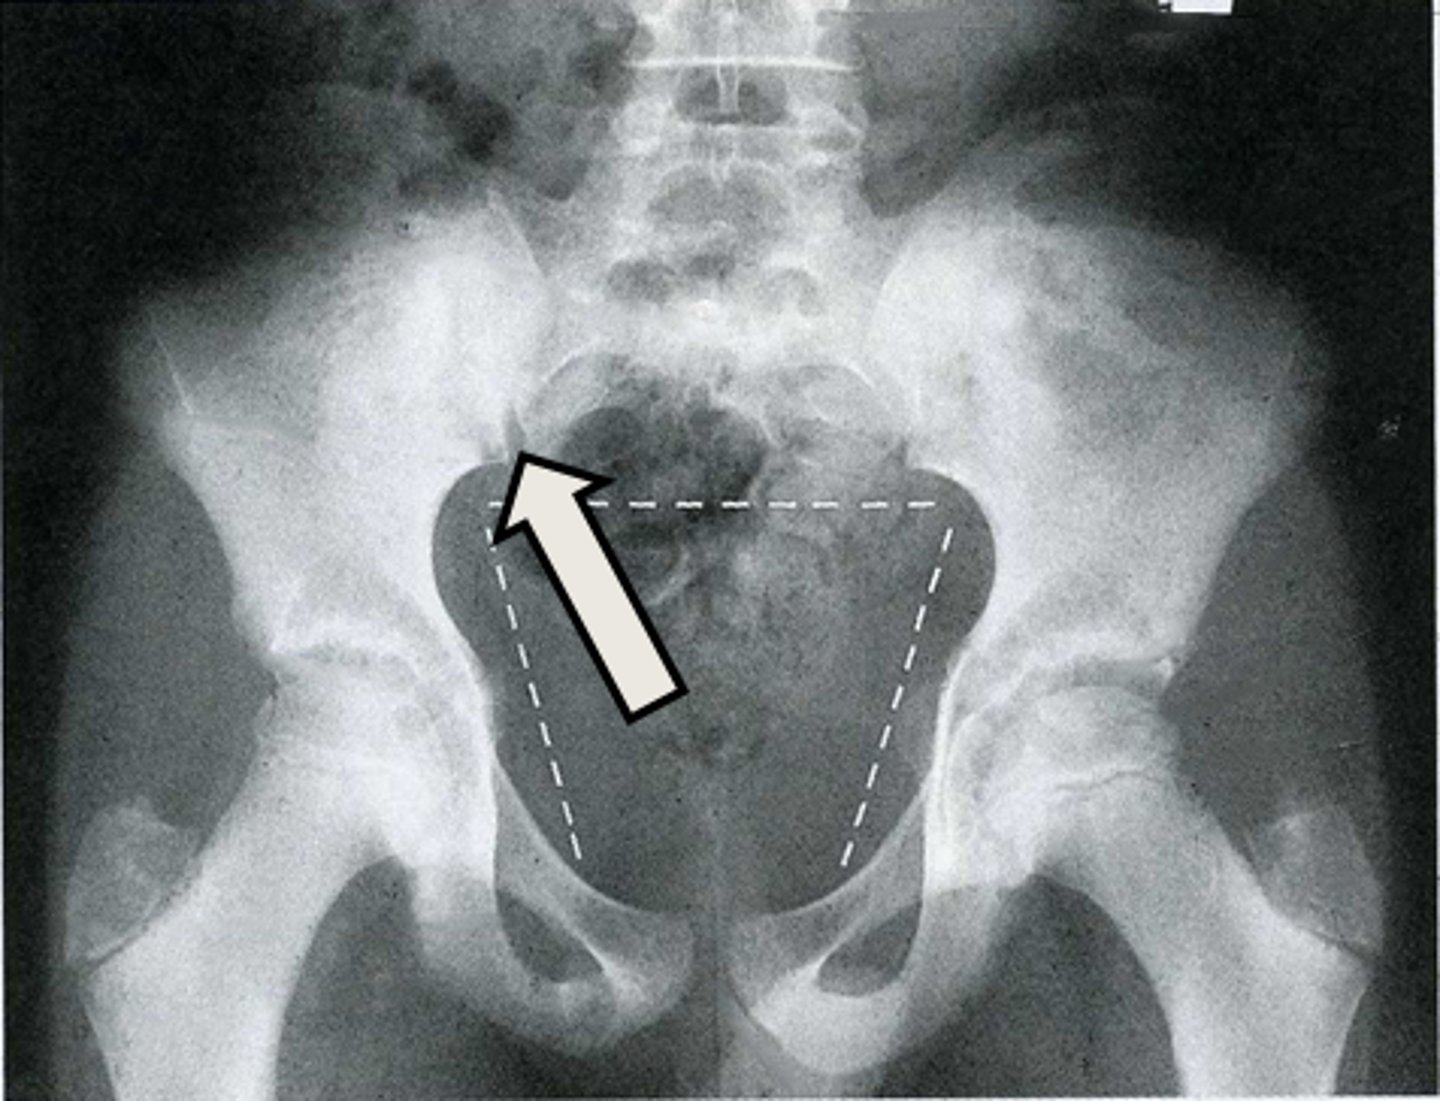

AP pelvis

What is the image?

2

Acetabulum

What is indicated in the image?

3

Body of L4

4

Epiphysial plate

5

Femoral head

6

Hip joint

7

Ilium

8

Ischial spine

9

Ischial tuberosity

10

Nonfused greater trochanter

11

Obturator foramen

12

Pubic symphysis

13

Sacroiliac joint

14

Sacrum

15